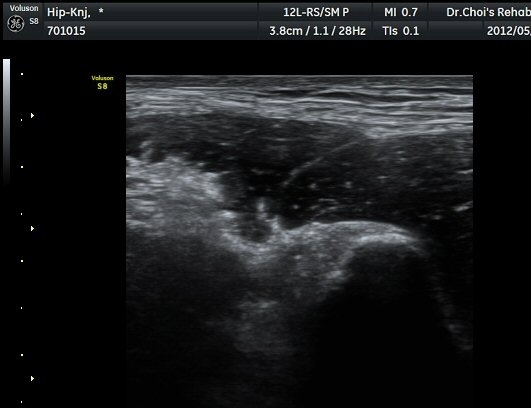

µÚÂÊ ´ëÅð ³»Ãø Ⱦ´Ü¸é°Ë»ç¿¡¼­ À̵ιڱ٠ÀåµÎ ¿ÜÃø¿¡¼­ ±ÙÀ°¼¶À¯¿Í ±Ù¸·¿¡ ÀÇÇØ Çü¼ºµÇ´Â

Á¤»óÀûÀÎ ±ÙÀ°ÀÇ ¸ð¾çÀÌ ¼Ò½ÇµÇ°í Àú¿¡ÄÚ º´º¯À¸·Î °üÂûµÈ´Ù(±×¸² 6). ŽÃËÀÚ¸¦ Á¶±Ý ¸»´ÜÀ¸·Î

À̵¿ÇÏ´Ï Àú¿¡ÄÚ º´º¯³»¿¡¼­ ±¹¼ÒÀûÀÎ ¼ö¾×Àú·ù°¡ °üÂûµÈ´Ù(±×¸² 7, 8).  À̵ιڱ٠ÀåµÎ Á¾´Ü¸é

°Ë»ç¿¡¼­ À̵ιڱ٠³»¿¡ ±¹¼ÒÀûÀÎ ±Ù¼¶À¯ ¼Ò½Ç°ú ¼ö¾×Àú·ù°¡ °üÂûµÈ´Ù(»çÁø 9, 10).